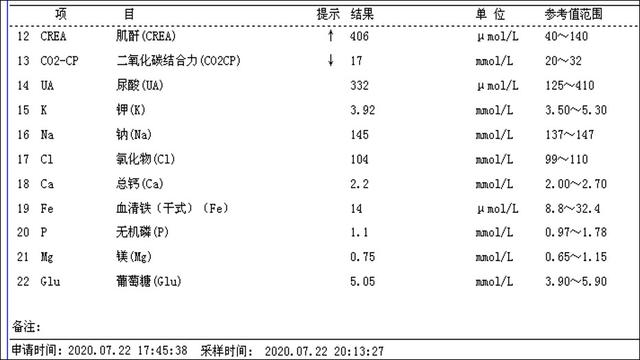

介入微创消融治疗后第一天甲状腺旁腺素降为486.2pg/ml(治疗前为3300pg/ml),静脉持续补钙血钙正常

介入微创消融治疗一周后甲状腺旁腺素降为333.3pg/ml(治疗前为3300pg/ml),静脉转换口服补钙血钙正常,全身骨痛明显好转。